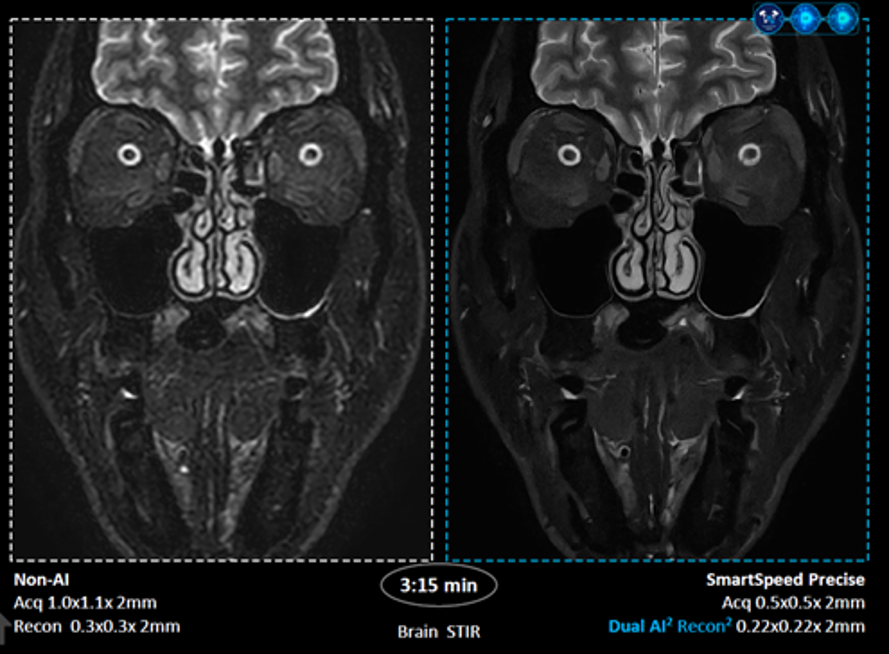

회사 측에 따르면 스마트스피드 프리사이즈(SmartSpeed Precise)는 필립스 MR 검사 시간 단축 기술인 ‘컴프레스드 센스(Compressed SENSE)’에 듀얼 AI 엔진을 적용해 검사 속도와 영상 품질을 동시에 크게 향상시킨다. 데이터 밸런싱 알고리즘과 필립스 고유의 AI 재구성 알고리즘이 원시 데이터(raw data) 단계부터 적용돼 중요한 신호만을 선별하고 반복 재구성 과정에서 불필요한 노이즈를 효과적으로 제거한다.

또한 초고해상도(Super Resolution) 알고리즘을 강화한 듀얼 AI 기능을 통해 기존 대비 이미지 해상도를 높여 신호대잡음비(SNR, Signal to Noise Ratio)를 개선하고, 링잉 방지(Anti-Ringing) 기능을 강화했으며 선명도(sharpness)를 최대 80% 향상한다. 듀얼 AI를 적용한 영상 재구성 방식으로 기존보다 최대 3배 빠른 검사 속도와 향상된 영상 품질을 동시에 구현한다.